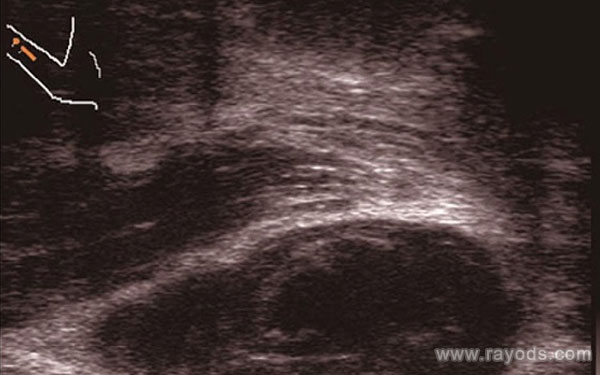

精索静脉曲张是一种血管病变,它指的是精索静脉出现异常的迂曲扩张的表现,多发于青壮年,当精索静脉曲张程度比较严重时,可能会对男性的精子产生影响,从而导致男性出现不育的症状。